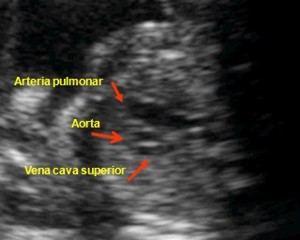

Este corte secciona horizontalmente los tres vasos: Arteria pulmonar, aorta y vena cava superior.

Estudia la disposición y el tamaño relativo de 3 vasos en un nivel ligeramente por encima del corazón: la arteria pulmonar, la arteria aorta y la vena cava superior. Estos 3 vasos se visualizan en la imagen y en el vídeo de tres vasos (hacer aquí clic para visualizarlo) cortados transversalmente y en disposición diagonal. Sus diámetros deben ser decrecientes; el mayor corresponde al tronco pulmonar y el menor a la vena cava superior (guiones amarillos). Cualquier anomalía en el número de estos vasos, en su disposición espacial o sus tamaños relativos debe hacernos sospechar la existencia de una cardiopatía congénita. De hecho, este corte nos permite diagnosticar o sospechar muchas de ellas.

Tres Vasos. Corazón normal |